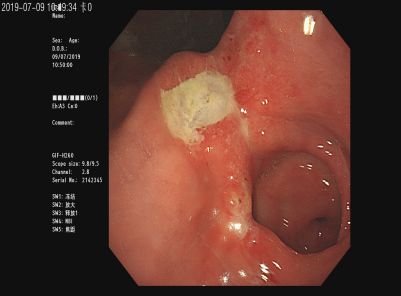

霉菌性食管炎

食管CA

胃角溃疡

胃镜检查术,俗称胃镜,是目前诊断上消化道(食管、胃、十二指肠)疾病最好的方法,对病变的观察清晰度优于任何其它影像技术,同时能对病变进行活体组织检查获得病理学诊断,并对早期上消化道癌、出血、狭窄、息肉等各种病变进行内镜下微创治疗术。我院消化内镜是省内开展胃镜及镜下微创治疗较早的单位,拥有最完善、最先进的内镜操作系统,每年完成胃镜诊治3万多例次。胃镜检查术简单、安全性好。大部分上消化道癌发现已经中晚期,因为多数早期消化道癌没有独特的表现,只有通过胃镜检查才能得到确切的早期诊断。50%早期消化道癌能够在胃镜下行局部病灶切除术(EMR、ESD),术后生存率可达90%。

早期胃癌能够内镜下切除!